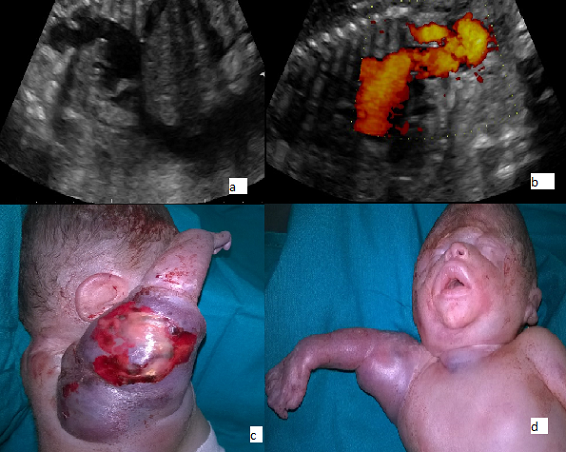

Nous rapportons le cas d’une patiente G3P3, adressée à notre Unité de diagnostic anténatal pour anasarque fœtoplacentaire à un terme de 31 SA associée à une rupture prématurée des membranes. L’échographie réalisée montrait un fœtus en anamnios, une anasarque fœtale, une mesure du pic systolique de vélocité au niveau de l’artère cérébrale moyenne >1.5 MoM et un épaississement cutané du membre supérieur droit évoquant une tumeur fœtale vascularisée. Le doppler énergie montrait le départ de vaisseaux de l’aorte communiquant avec l’artère sous clavière droite (A,B). Deux heures après l’hospitalisation, la survenue d’une souffrance fœtale aigue a imposé un accouchement par césarienne. L’examen du nouveau-né de sexe masculin montrait une tumeur vascularisée prenant et déformant tout le membre supérieur droit, allant jusqu’à la partie haute du thorax (C,D). Un thrill a été objectivé à la palpation, confirmé par la présence d’un souffle au niveau de la tumeur, témoin de shunts artério-veineux. Le décès du nouveau-né est survenu 30 minutes après la naissance malgré une réanimation néonatale active.